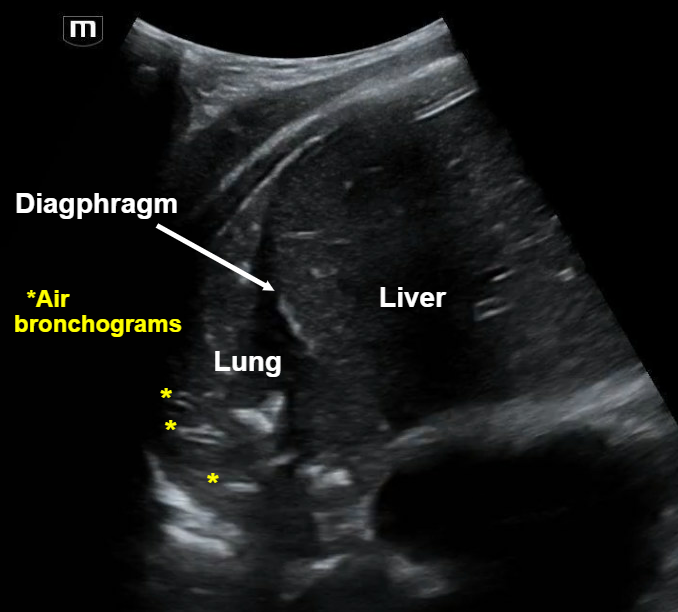

Patient is a 70-year-old M with PMH of DM, HTN, HLD presenting for 2 days of chest pain, abdominal pain, dizziness, shortness of breath, and cough.